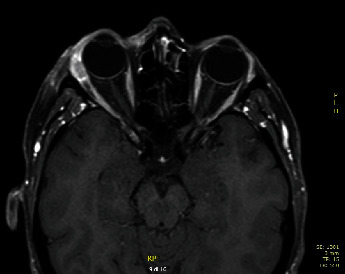

背景:泪腺上皮性肿瘤非常罕见,泪腺原发性导管腺癌仅占所有泪腺上皮性肿瘤的 2%。考虑到其罕见性和缺乏统一的诊断标准,治疗方案也没有得到很好的界定。在本研究中,我们描述了一例 Her-2 阳性病例,并回顾了之前报道的病例。研究方法2012年,一名42岁的女性患泪腺原发性导管腺癌,她接受了经眼球前眶切除术和辅助放疗。2013 年 7 月,她出现局部复发,于是接受了眼眶外扩张术。2013年11月,因颈部结节进展,她接受了7个周期的化疗(顺铂和表柔比星),同时使用人源化单克隆抗体靶向HER 2疗法(曲妥珠单抗和百妥珠单抗),取得了明显的反应率。随后,她接受了腮腺全切除术和右颈部淋巴结切除术,并接受了辅助性甲状腺治疗。结果:治疗结束九年后(113 个月),患者无病存活,毒性反应可接受。结论对于泪腺原发性导管腺癌,考虑到其往往具有侵袭性,早期诊断和多模式治疗至关重要。考虑到缺乏治疗指南,病例报告记录有助于患者的管理。

Background: Epithelial tumors of lacrimal glands are rare and primary ductal adenocarcinoma of the lacrimal gland accounts for only 2% of all epithelial lacrimal gland tumors. Considering its rarity and lack of uniform diagnostic criteria, treatment protocols are not well defined. In this study, we describe a Her-2 positive case and review previously reported cases. Methods: In 2012, a 42-year-old woman affected by primary ductal adenocarcinoma of the lacrimal gland was treated with transpalpebral anterior orbitotomy and adjuvant radiotherapy. In July 2013, she presented local relapse and she underwent orbital exenteration. In November 2013, for neck nodal progression, seven cycles of chemotherapy (cisplatin and epirubicin) associated with a humanized monoclonal antibody-targeting HER 2 therapy (trastuzumab and pertuzumab) were performed, with a marked response rate. Then, she underwent total parotidectomy with right neck lymphadenectomy and adjuvant hadrontherapy. Results: Nine years later (113 months) after treatment completion, the patient was alive without disease and with acceptable toxicity. Conclusions: In primary ductal adenocarcinoma of the lacrimal gland, early diagnosis and multimodal treatments could be crucial, considering its often aggressive tendency. Considering the lack of treatment guidelines, case report recording can be useful in patient management.